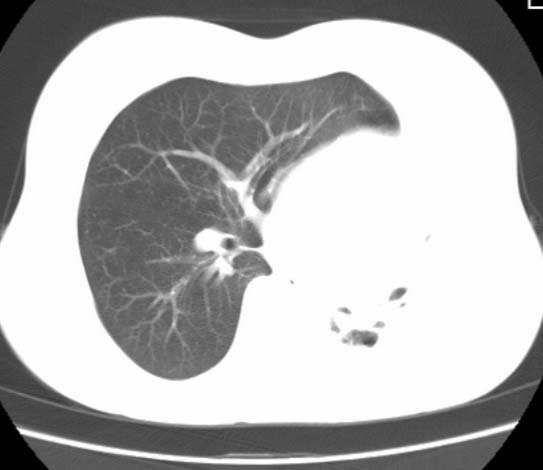

标题: CT25648:求教:是肺发育不全还是结核?

女  20岁。一月前咳血,诊“肺结核”抗痨治疗一月后,咳血停止,现复查。病人精神好。前后ct片对比未见明显变化。既往体检“正常”

1)考虑左肺结核并肺不张、支气管扩张。2)纵隔疝。

考虑左肺结核,左肺毁损,纵膈左偏,既往体检正常不可靠,tb一个月也不会这个样子的,有钙化,应该病程较长,冰冻三尺非一日之寒!

左肺发育不全。